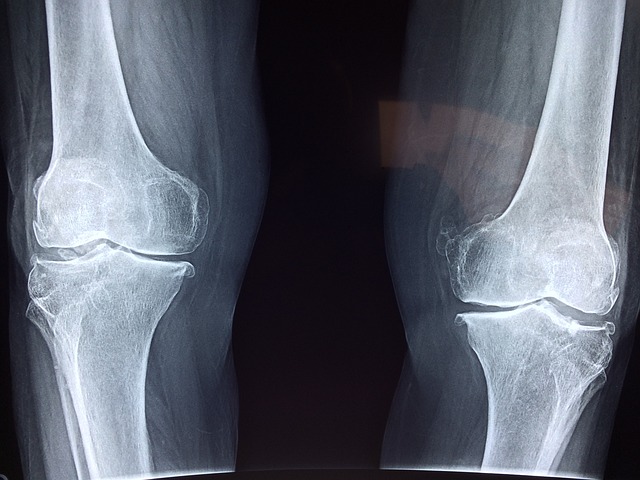

무릎 관절 수술: 원인부터 회복까지

무릎 관절은 우리 몸에서 가장 큰 관절 중 하나로, 일상생활에서 굉장히 중요한 역할을 합니다. 때로는 다양한 이유로 인해 수술이 필요할 수 있는데, 이에 대해 자세히 살펴보겠습니다.

무릎 관절 수술이 필요한 원인은 다양합니다. 주된 원인 중 하나는 관절염으로, 골관절염과 류마티스 관절염이 여기에 속합니다. 이 외에도 외상, 연골손상, 무릎관절의 선천적 이상 등이 수술의 원인이 될 수 있습니다.

무릎 관절 수술에는 다양한 유형이 있지만 가장 흔한 것은 무릎 관절 치환술입니다. 이 수술은 손상된 무릎 관절을 인공 관절로 대체하는 것을 목표로 합니다. 수술은 전신마취 하에 진행되며, 수술 후에는 물리치료와 재활 프로그램을 시작하여 조기 회복을 돕습니다.